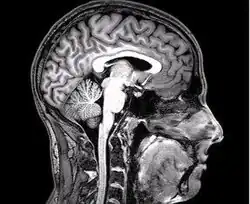

Although there have been many debates on the actual definition of compassion (Gilbert, 2019), whether it is an emotion or a complex construct, it has been consistently shown that compassion can be shown neurologically (Kim et al., 2020). Through the first meta-analysis conducted on compassion, comprising of 16 peer reviewed articles (Kim et al., 2020), brain activation was found consistent in brain region through across multiple studies. In the meta-analysis Kim et al. used a software called GingerALE which would locate above-chance clustering of the foci between experiments, using an estimation likelihood estimation (ALE) (Laird et al., 2005). This software provided cluster size, location, and anatomic labelling. Although the software could analyse above-chance foci clustering, not all experiments were consistent in their testing measures, this caused the 16 articles to be broken up into subcategories which were then tested against one another for a more accurate reading on brain activation.

ALE had found that seven regions of the brain showed consistent activation across multiple of the studies included in the meta-analysis being the Anterior Cingulate, Bilateral Inferior Frontal Gyrus, Bilateral Insula, Middle Frontal Gyrus, Medial Frontal Gyrus and Basal Ganglia/Thalamus circuitry (Engström & Söderfeldt, 2010; Kim et al.,2020; Mascaro et al., 2012).

Out of the seven regions, two were found to have the most significant activation (Kim et al. 2020). The Anterior Cingulate Cortex and the Anterior Insula. The anterior Cingulate Cortex is responsible for the important cognitive roles, such as decision making and impulse control but has also been determined to play a role in the emotion of empathy (Stevens et al., 2011). The Anterior Insula is geared more towards the breaking down of negative sensory input, this region of the brain, although considered one of the least understood areas, has shown activation during negative visual stimuli (Uddin et al., 2017). These two regions are considered integral parts of the salience network. The salience network is usually tapped into when a person experiences or observes another’s pain (Cao et al., 2017). The activation of these regions was primarily found throughout stimulus tasks, consisting mostly of the presentation of negative stimuli, but was also found through mindset tasks, through tapping into past experiences (Kim et al., 2020).